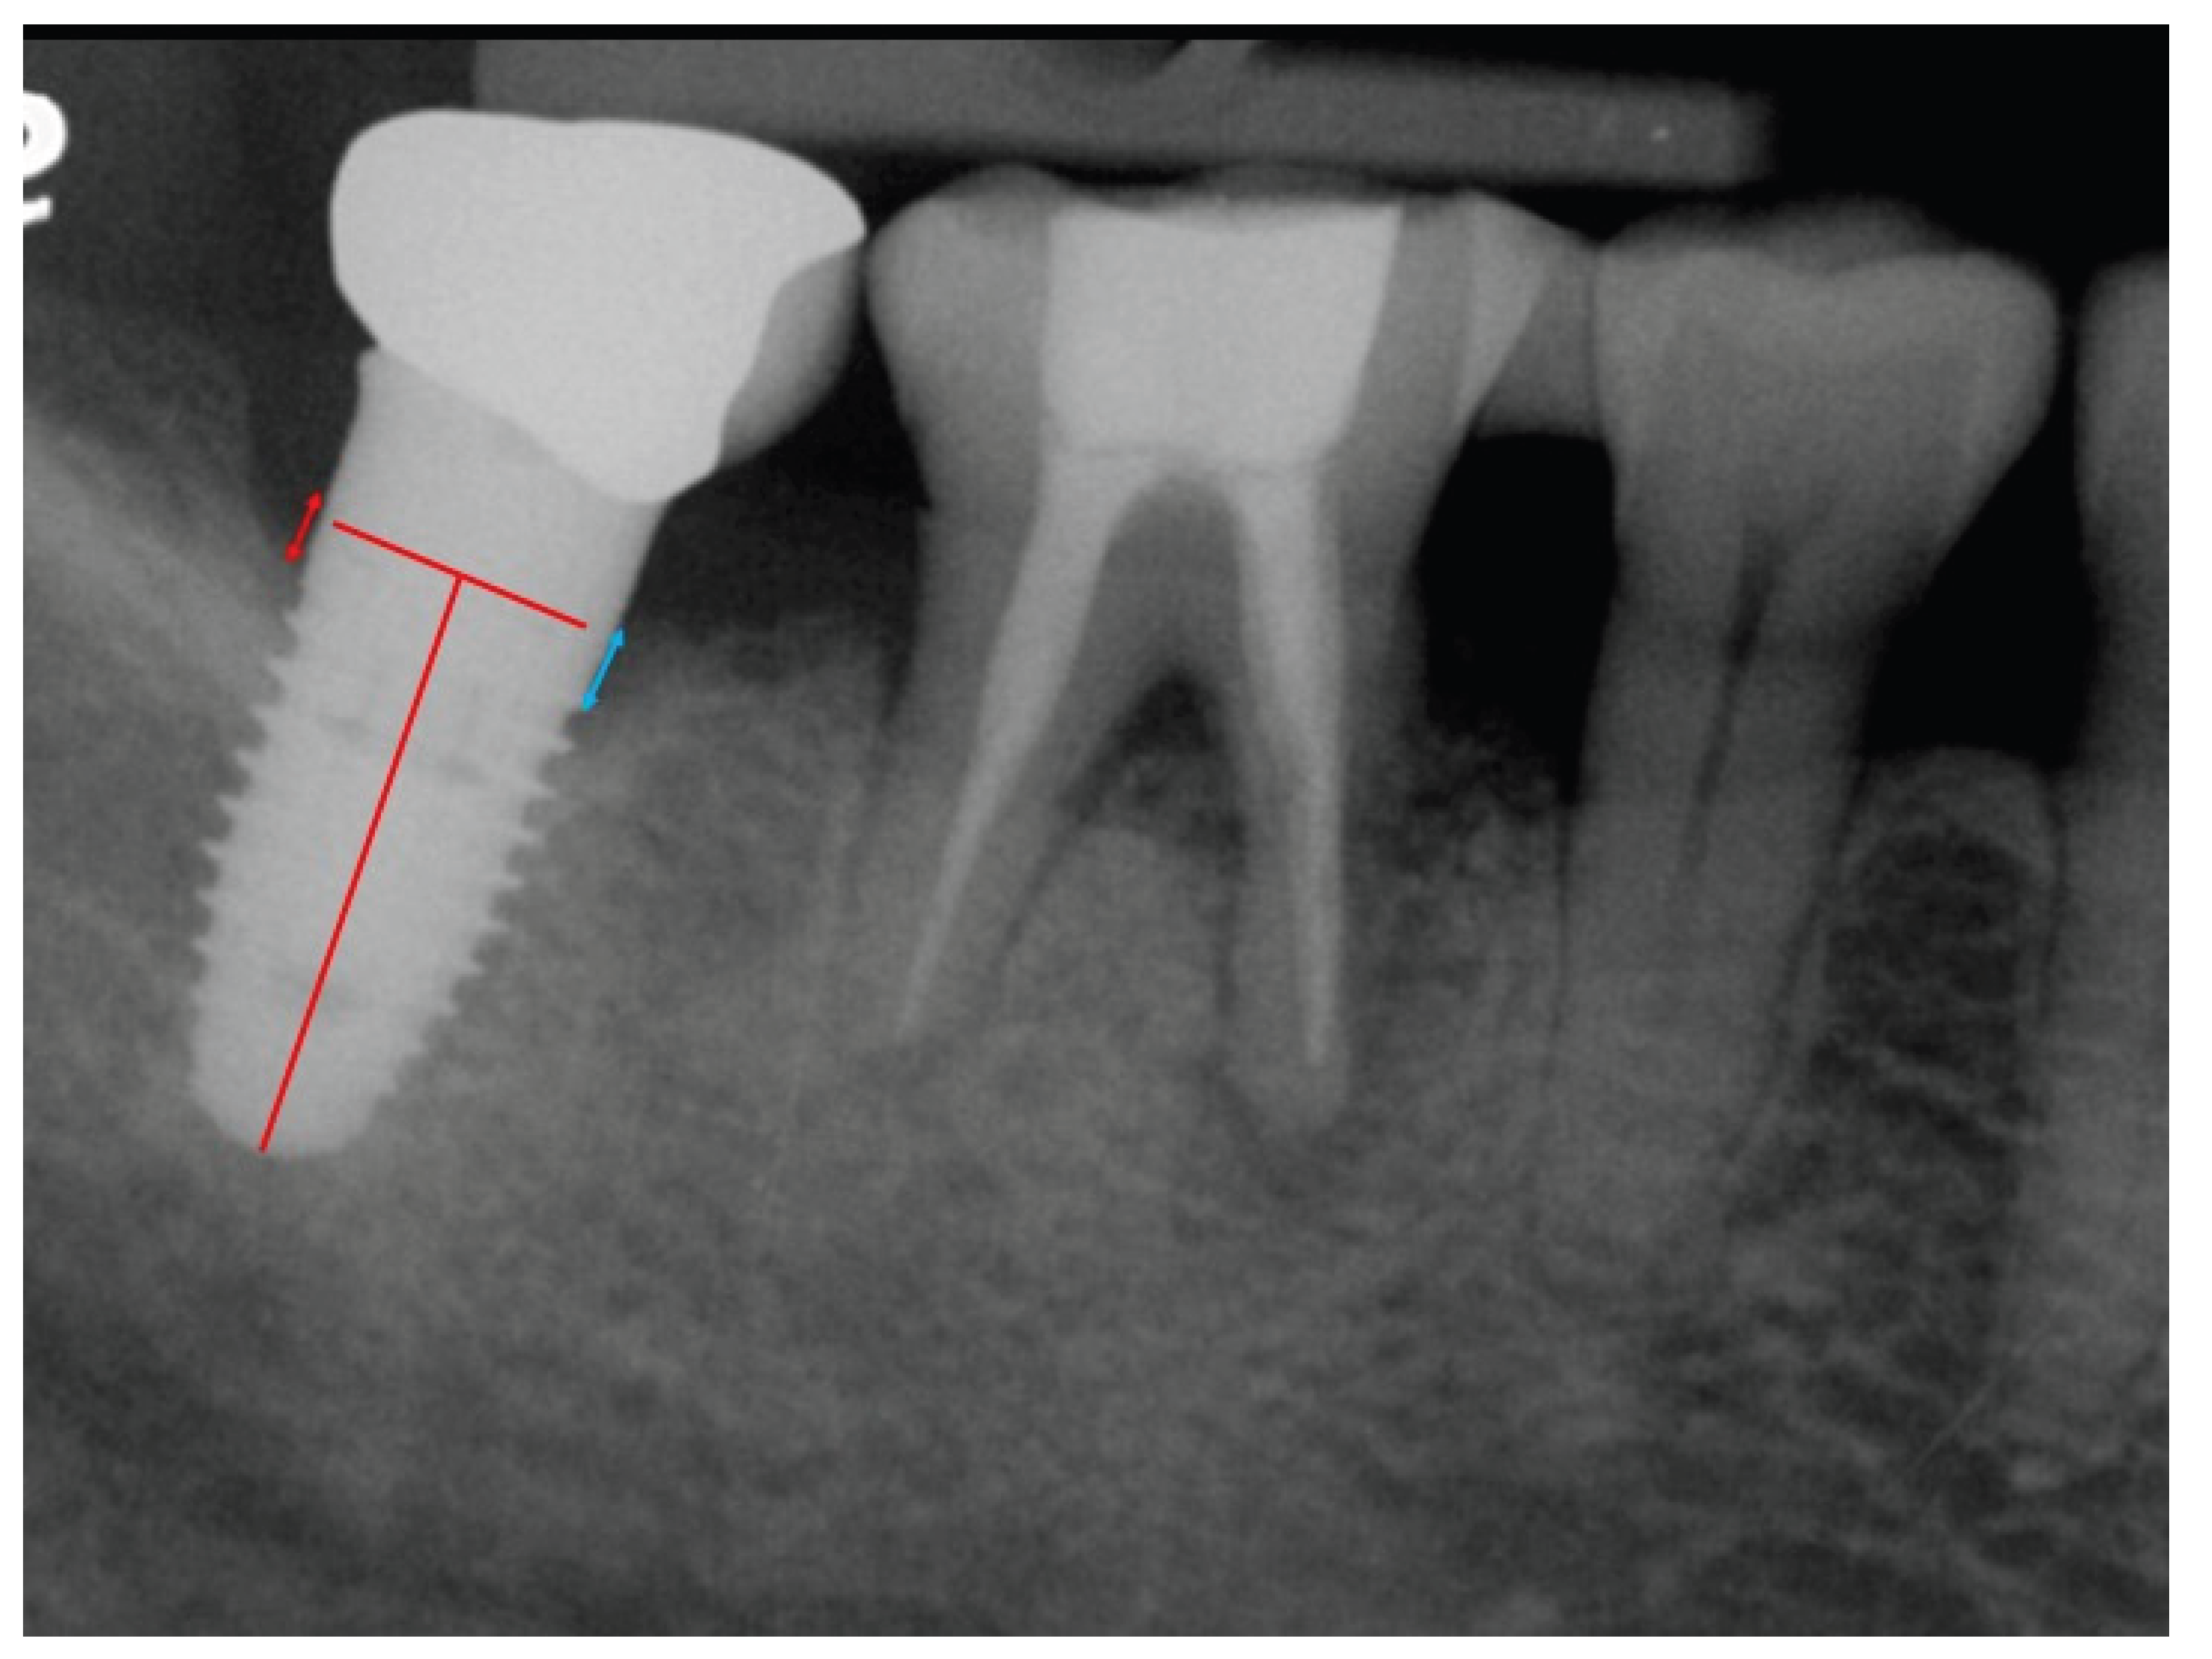

Baseline periapical radiographs were obtained at the initiation of orthodontic therapy with implants as reference for the MBL measurements. Radiographic assessments of the MBLs around the implants were conducted using digital imaging software (Infinitt Radiology PACS, Taipei, Taiwan). The MBL was measured from the crown margin to the alveolar bone crest (Figure 3). Both the mesial and distal bone levels were measured at the time of crown delivery (points a and b) and at the final follow-up (points c and d). The mean bone level for each implant was calculated as the mean of the mesial and distal measurements. The distortion ratio was used to adjust radiographic assessments for a coefficient derived from the true implant length/radiographic implant length ratio to account for radiographic distortion and magnification. Total bone loss was calculated by subtracting the baseline average bone level (a+b)/2 from the final follow-up average bone level (c+d)/2.

Figure 3. Measurement of marginal bone level. The marginal bone level was measured from the crown margin to the bone crest. Both the mesial and distal implant bone levels at crown delivery (a, b) and at follow-up (c, d) were measured. The mean mesial and distal bone levels were calculated as the average bone level for each implant. Average total bone loss was measured by deducting the baseline mean bone level (a+b/2) from the last follow-up bone level (c+d/2).